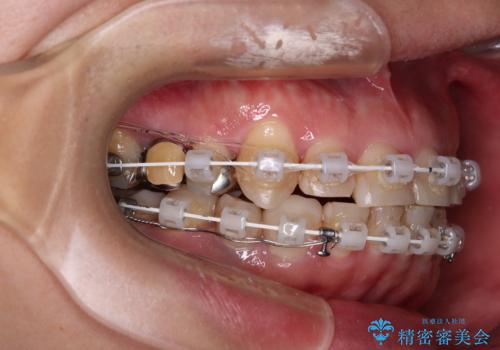

抜歯が必要な歯は事前に抜歯をし、その後ワイヤー装置にて歯列矯正を行い、途中でインプラントを埋入し、オールセラミッククラウンにて補綴治療を行うこととしました。

矯正治療にやや時間がかかりましたが、歯列はきれいに整い、気になっていたむし歯や銀歯は自然な色合いに仕上がりました。